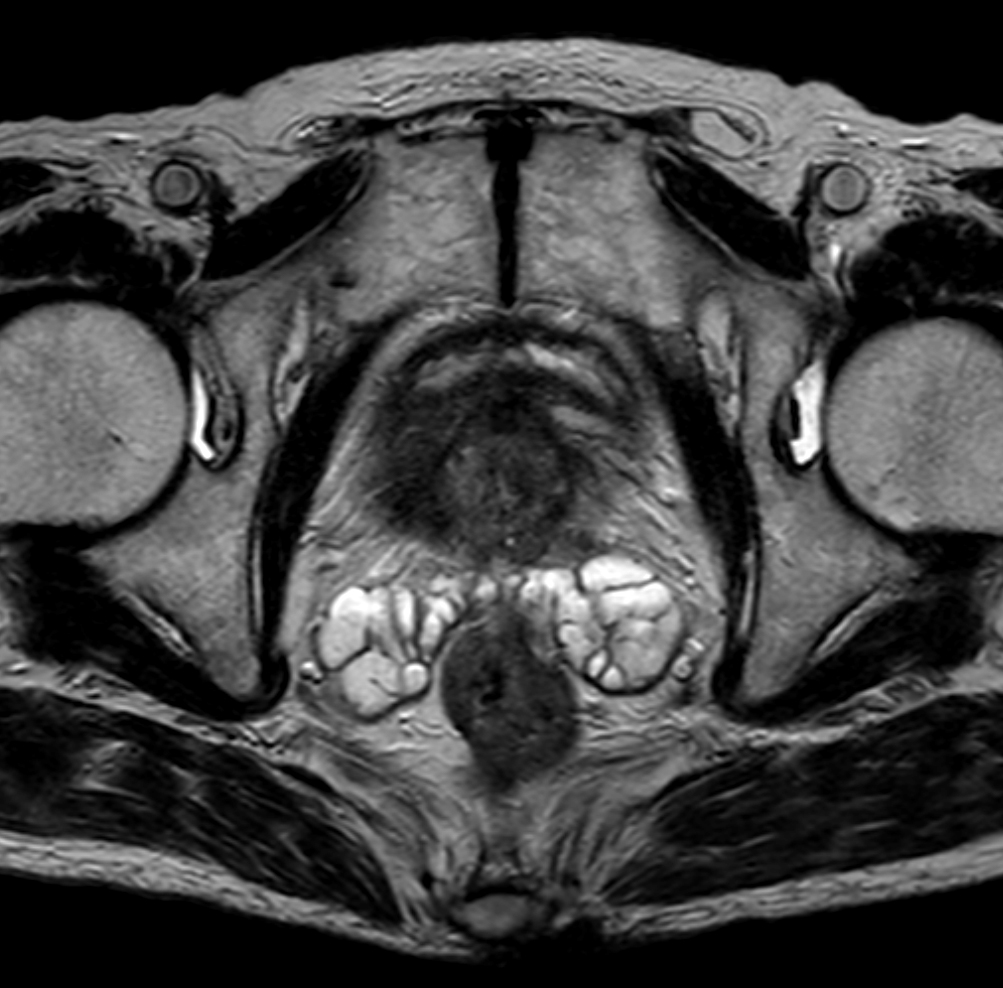

Axial T2w TSE